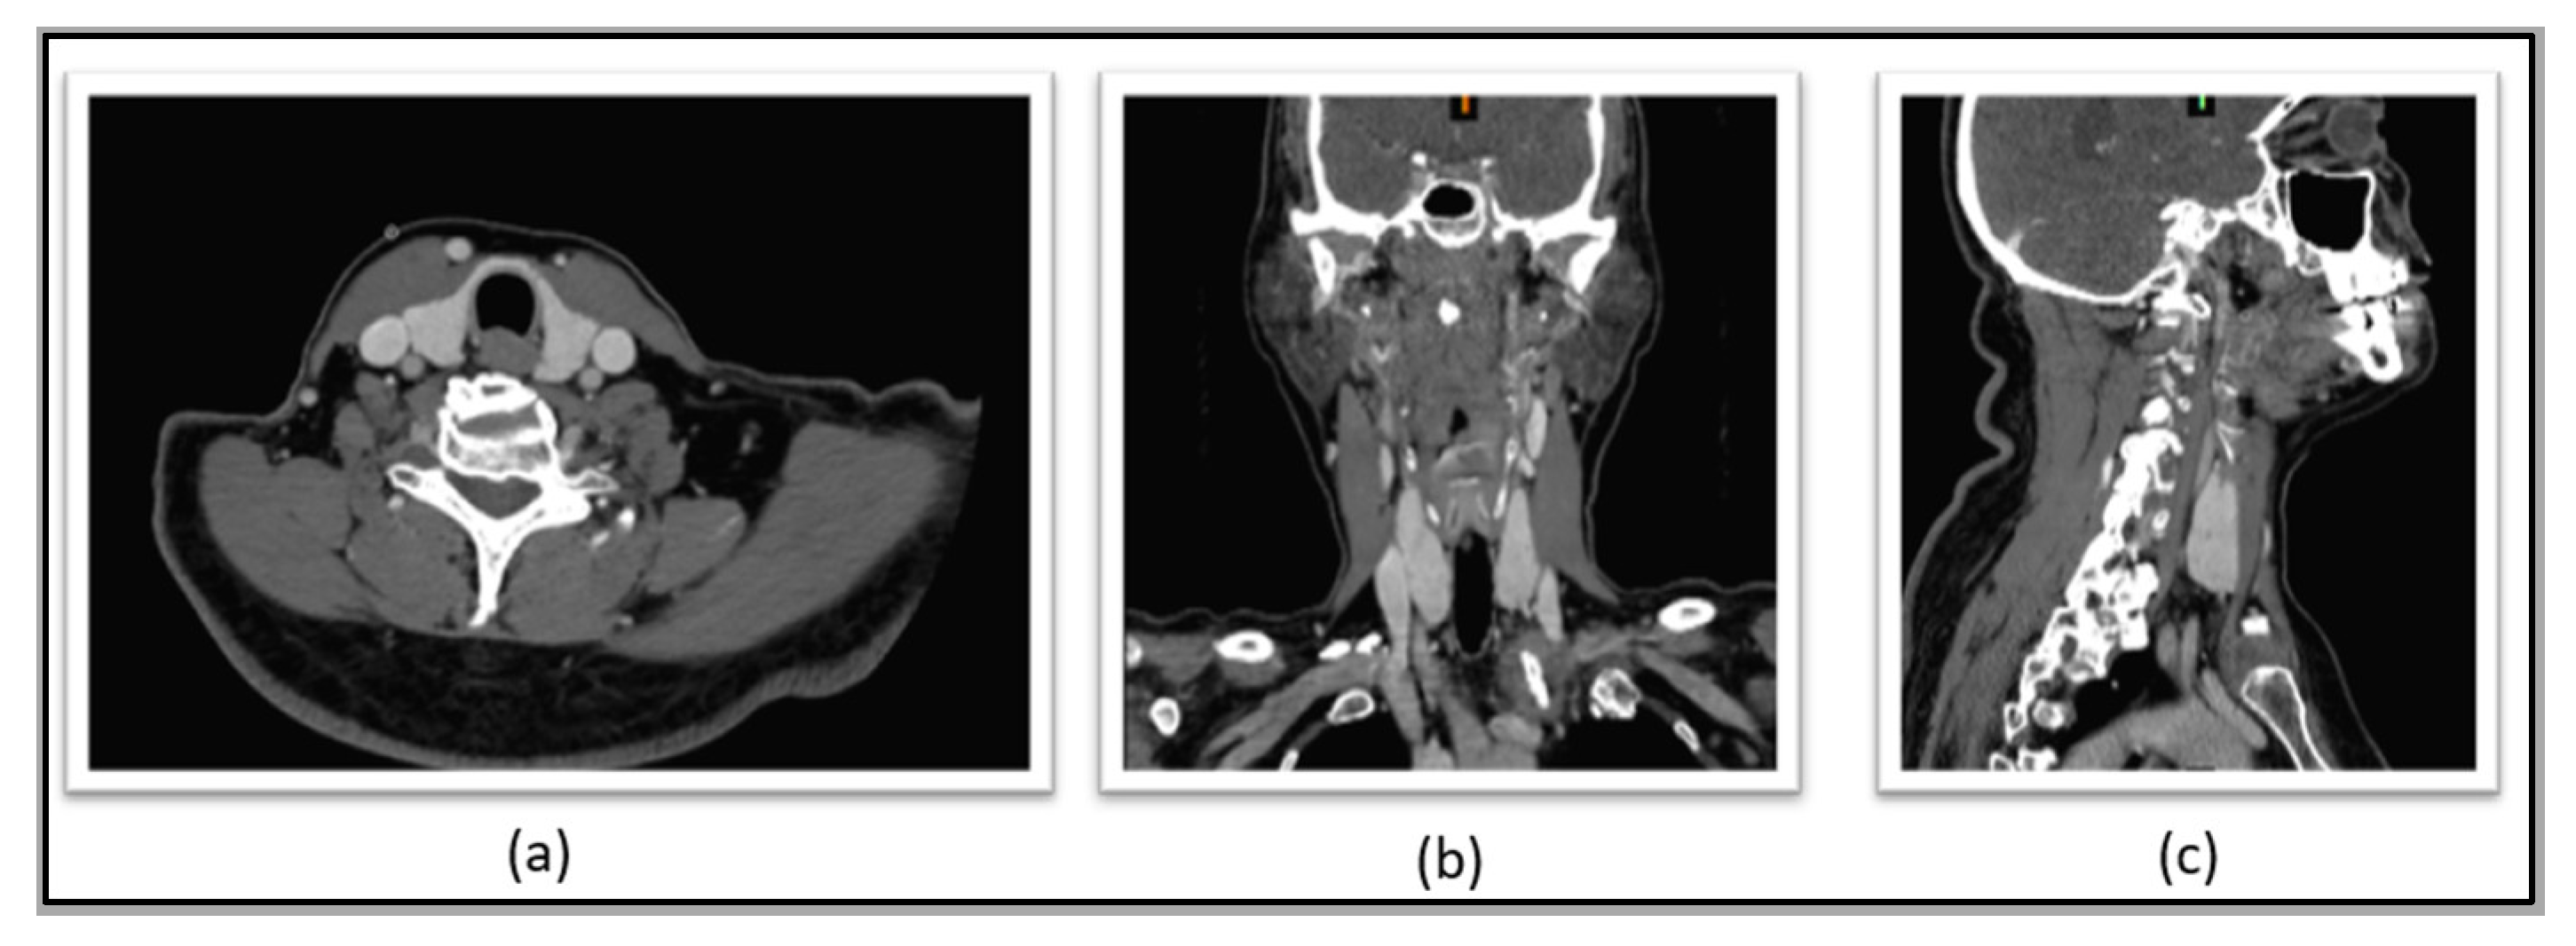

3.2.1. Segmentation of the Neck Region and Inner Structures

4.1. Segmentation Results